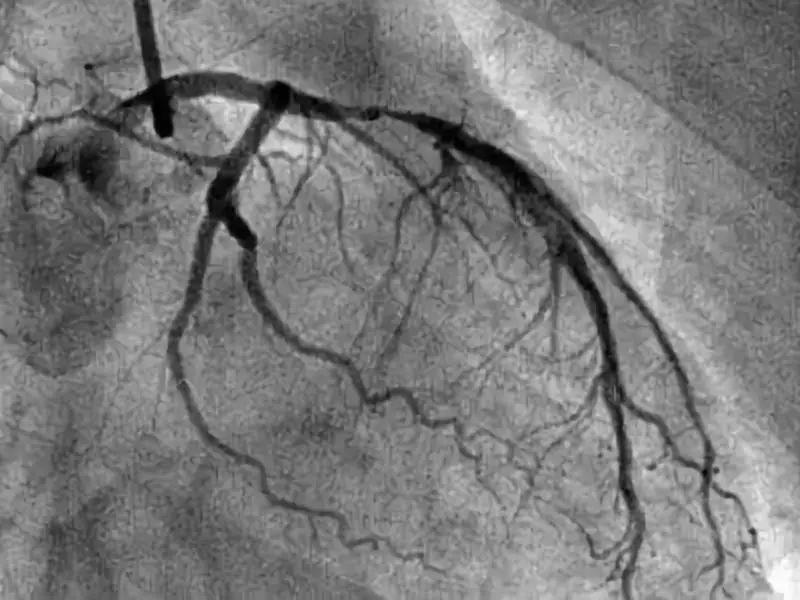

冠脉造影检查,是一种针对冠心病检查的重要方法,它的有效率非常高,能准确且清晰的显示患者冠状动脉的解剖结构以及它可能存在的畸形、阻塞性位置,是目前唯一也是最先进的心血管检查方式。

第一,冠脉造影技术,需要在患者体内插入一根长长的导管。在检查时,医生要把细管插入患者体内,然后在导管里倒入“造影剂”,为的是X光线能捕捉到冠脉的形态学表现。

冠脉造影,有一项是看患者的冠脉血流分级:

0级,无灌注,患者冠脉闭塞部位及远端无造影剂充盈。

1级,造影剂通过闭塞部位,但是远端血管无造影剂。

2级,造影剂能抵达远端血管,但是速度缓慢。

3级,造影剂快速抵达远端血管。

通过分级,可以一定程度判断狭窄程度。另外,医生建议如果你要去做冠脉造影,前一天一定要做好准备,首先要休息好,以免在做冠脉造影时出现意外。